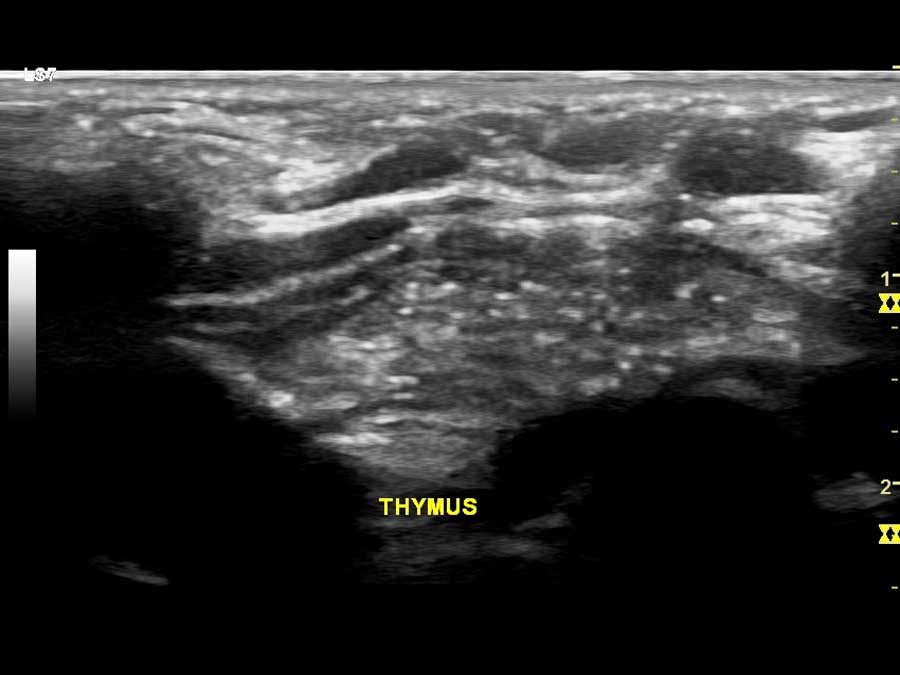

- Υπερηχογράφημα τραχήλου (συρίγγια, συγγενείς κύστεις, βραγχιακά υπολείμματα, κύστη θυρεογλωσσικού πόρου, έκτοπος θυμικός ιστός, βλάβες λεμφικού ιστού κ.α.)

Στο Ιατρείο Υπερήχων Παιδιών & Ενηλίκων χρησιμοποιείται η Ελαστογραφία (SE) στη μελέτη:

- όγκων ή μορφωμάτων σιελογόνων αδένων (παρωτίδα, υπογνάθιος αδένας),

- μορφώματα στο μαστό,

- επιφανειακές βλάβες στον υποδόριο ιστό.

Γενικά η Ελαστογραφία χρησιμοποιείται ως συμπληρωματικό «εργαλείο» στον υπερηχογραφικό έλεγχο όλο και περισσότερο τα τελευταία χρόνια. Η ειδικότητα της μεθόδου εξαρτάται από την εμπειρία του εξεταστή.